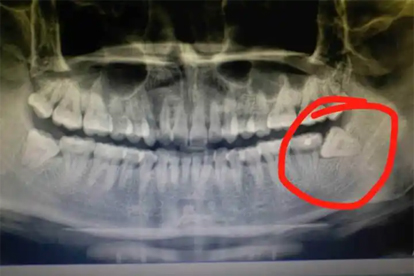

智齿位于牙列最末端,上下左右各一颗,共四颗。萌出时可能出现阻生、倾斜或仅部分萌出,容易导致邻牙龋坏、牙龈发炎或囊肿。第二磨牙则是恒牙列中正常的第二颗臼齿,12岁左右萌出,形态规则且功能稳定。两者可通过口腔X光片明确区分,智齿牙根常较短或分叉不规则。